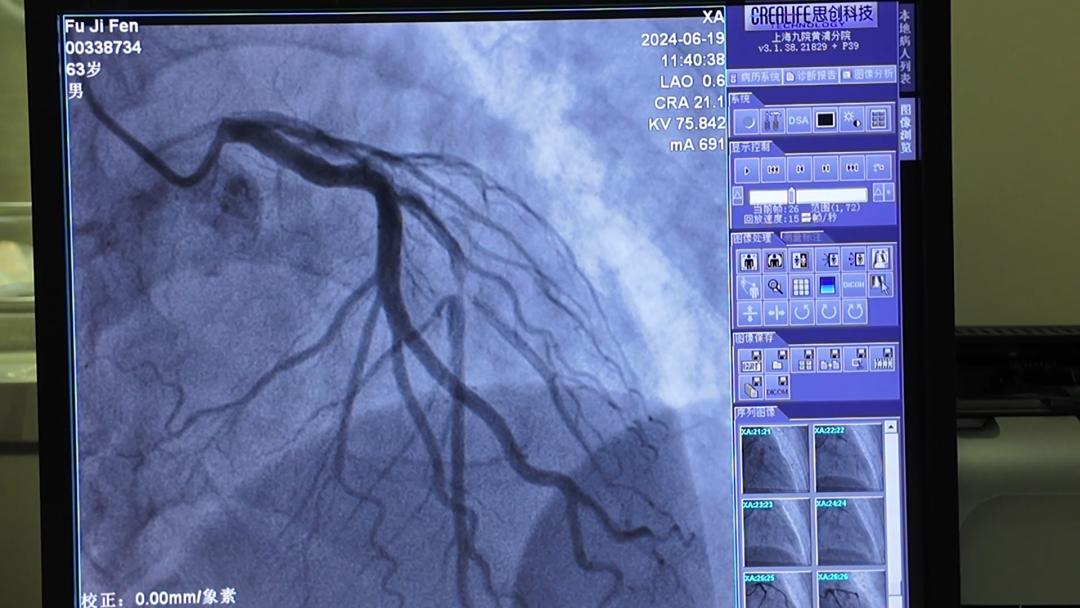

体检中心工作人员迅速推动轮椅,让傅先生坐在上面,通过绿色通道畅通无阻地送到医院的急诊胸痛中心。根据心电图结果,医生立即为傅先生安排了冠状动脉造影检查。检查结果显示,傅先生的血管支系严重狭窄,达到90%,情况非常危急。

心血管内科副主任医师徐宗雨迅速赶到现场。他立即为傅先生进行了紧急治疗,并植入了一个支架,成功打开了狭窄的血管。徐医生说,90%的狭窄意味着冠状动脉容易再次堵塞。一旦堵塞,心脏就会坏死,危及生命。幸运的是,血管及时打开,否则后果不堪设想。